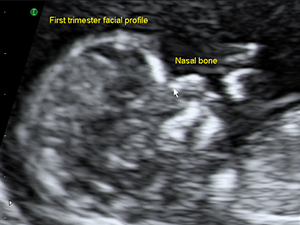

早孕期側面輪廓